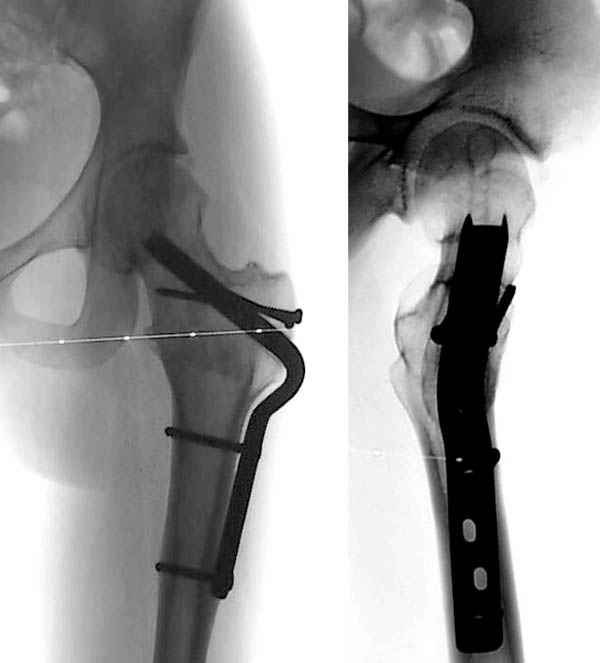

Здесь представлен один из случаев остеотомии на шейке после остаточного явления юношеского эпифизиолиза из Flip Trochanteric доступа.